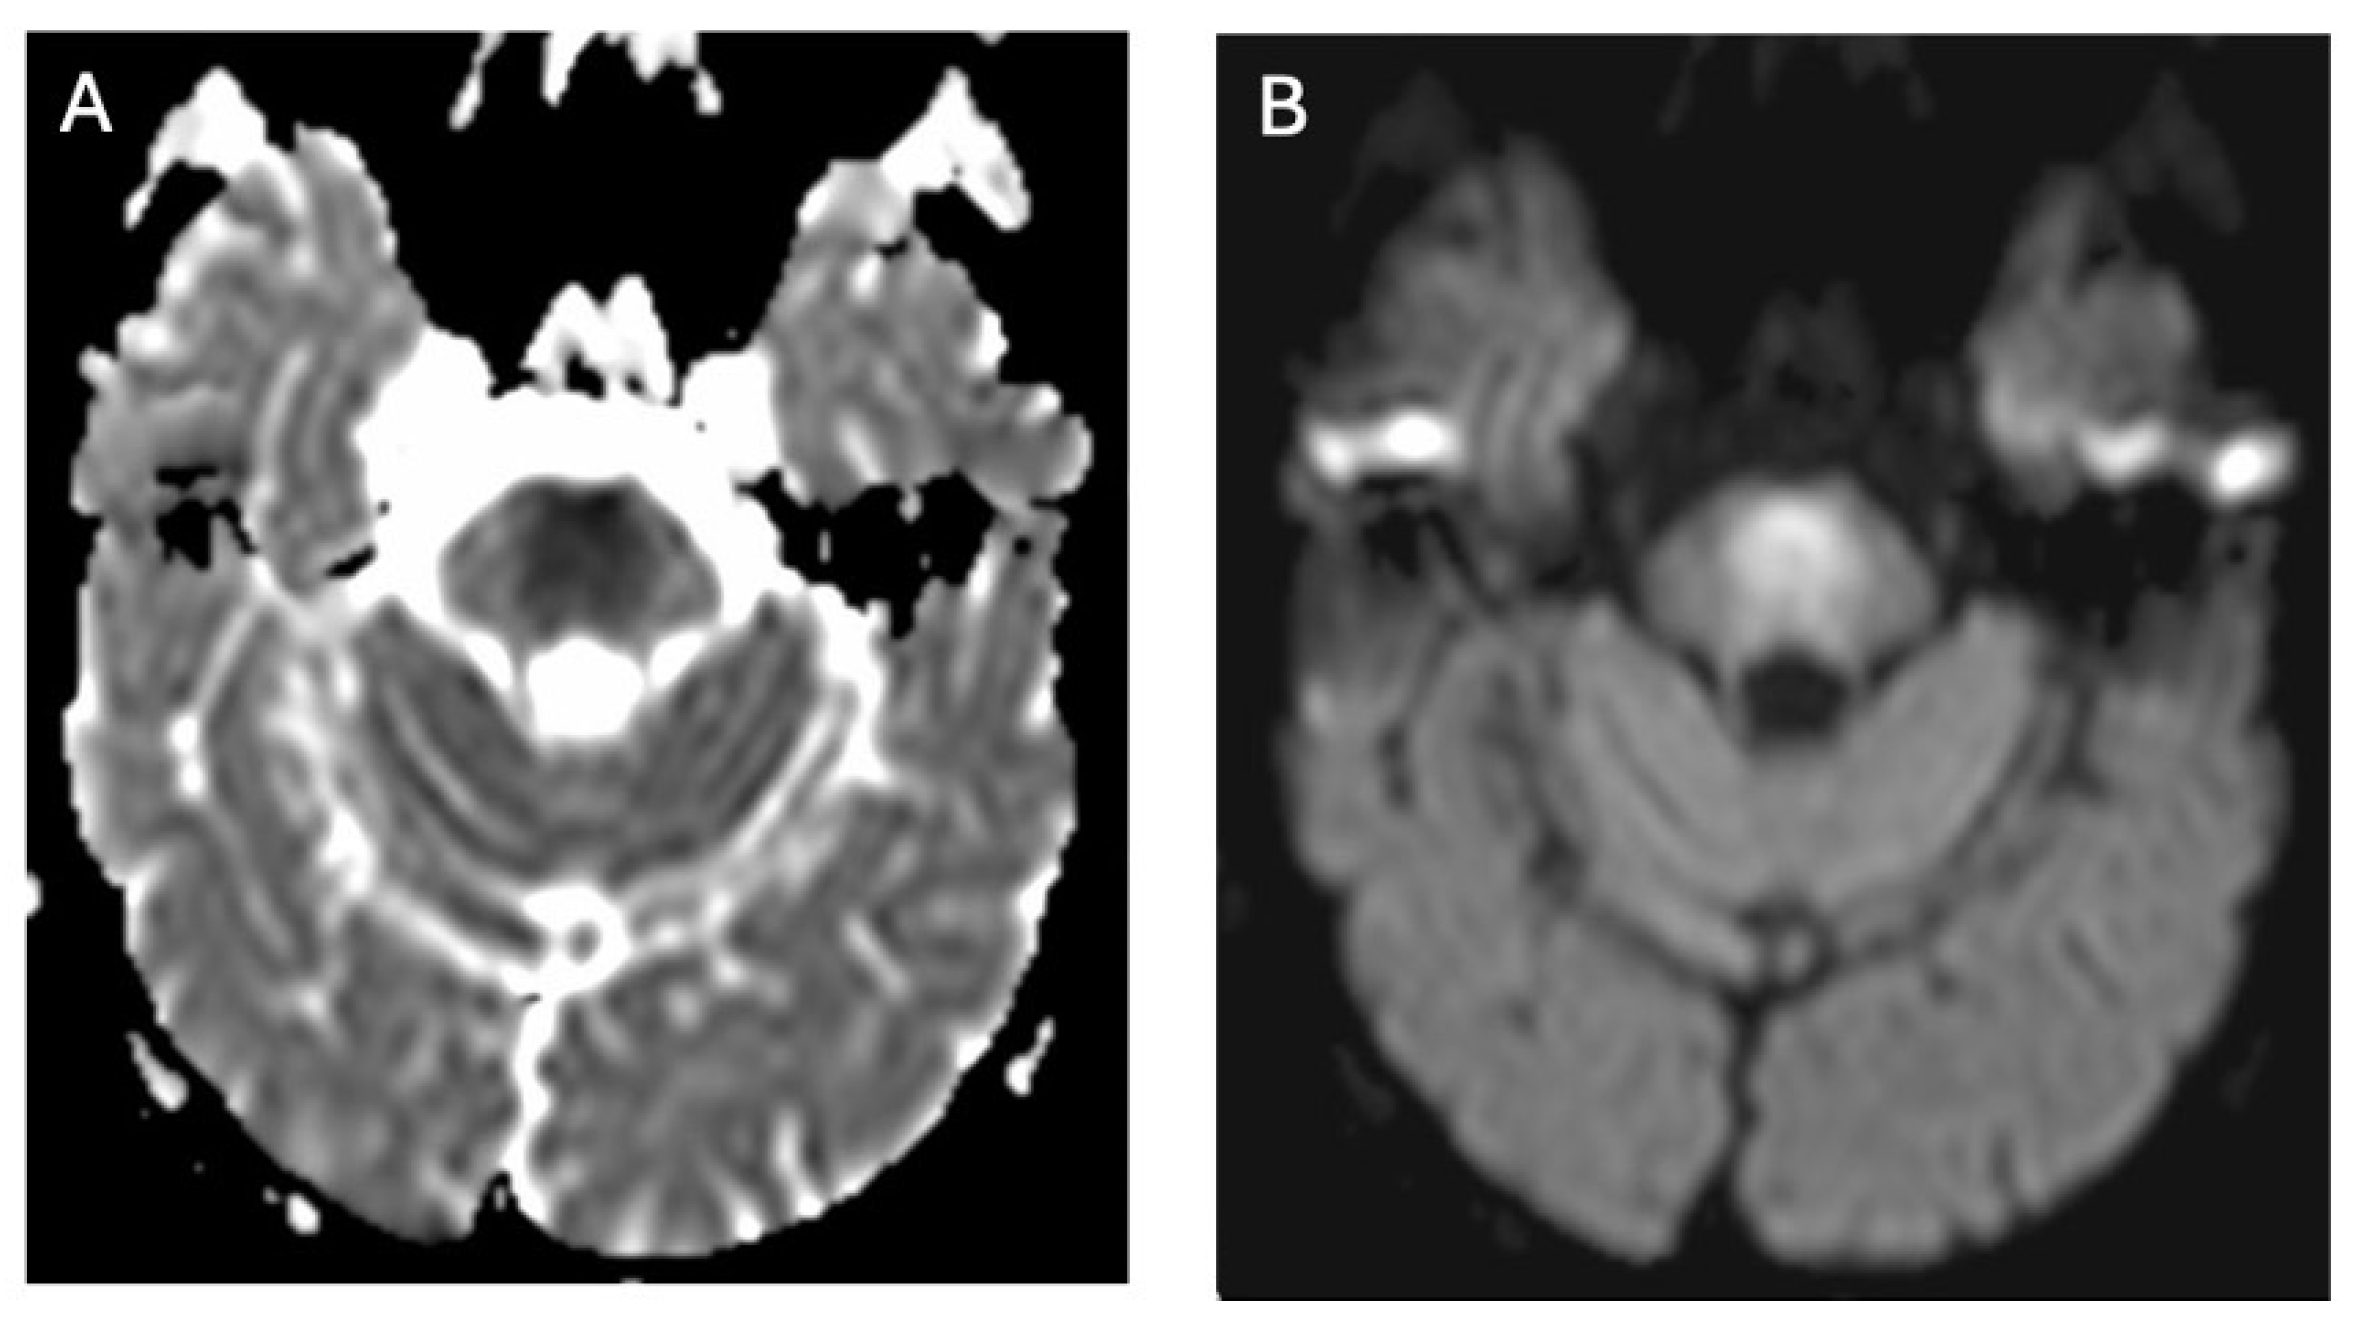

3.2. Diffusion MRI in WD